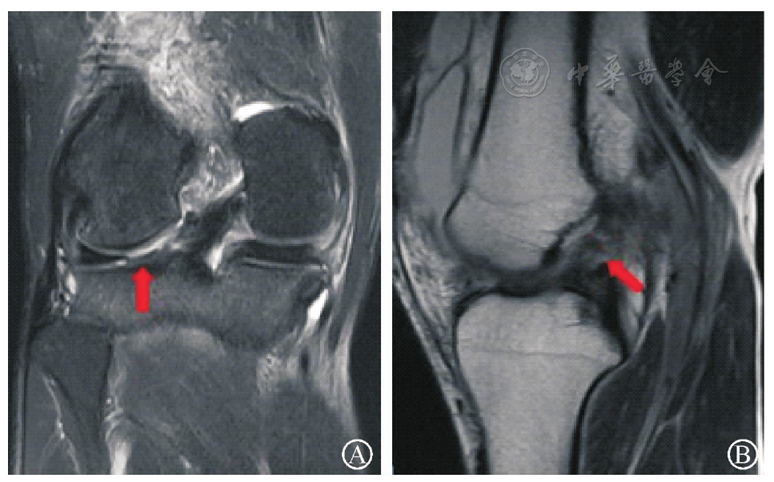

图3 LMPHRT(外侧半月板后根部撕脱)合并ACL(前交叉韧带)损伤术前膝关节MR图像。图A为膝关节冠状位MRI,红箭头示LMPHRT;图B为膝关节矢状位MRI,红箭头示ACL损伤